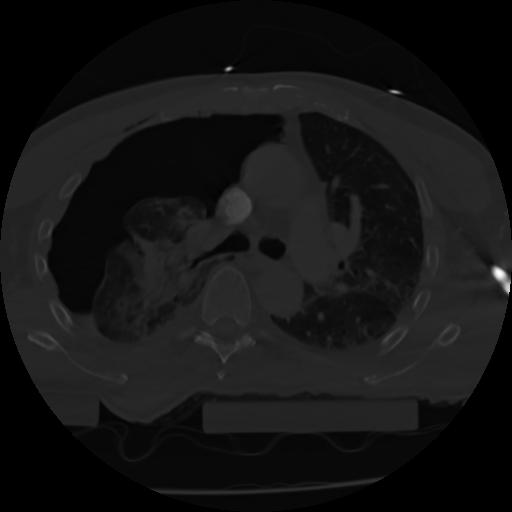

21 ANGIO,CE,Axial,3.0,ANGIO,,